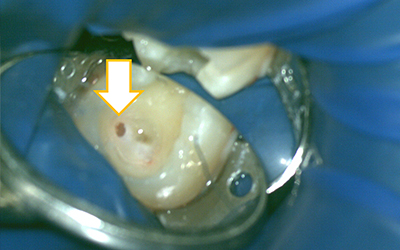

マイクロスコープで直接神経の状態を確認することです。

ポルトランドセメントを主成分とする薬で、このセメントを使う事により本来なら神経を取らざる得ない場合でも神経の保存が可能になりました。